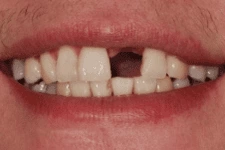

3. 即拔即種

打破傳統即拔即種(又叫立即植牙),拔牙後立刻植牙。患者可在拔牙後立即植入人工植體,並立刻裝戴假牙。讓你治療當天就能擁有美觀的門面。

我們在植牙領域的突破,克服患者對手術的恐懼,也同時幫助患者告別了缺牙的痛苦,讓患者重新擁有一口完美的牙齒。

↑ 治療後:微創立即植牙恢復美麗外觀